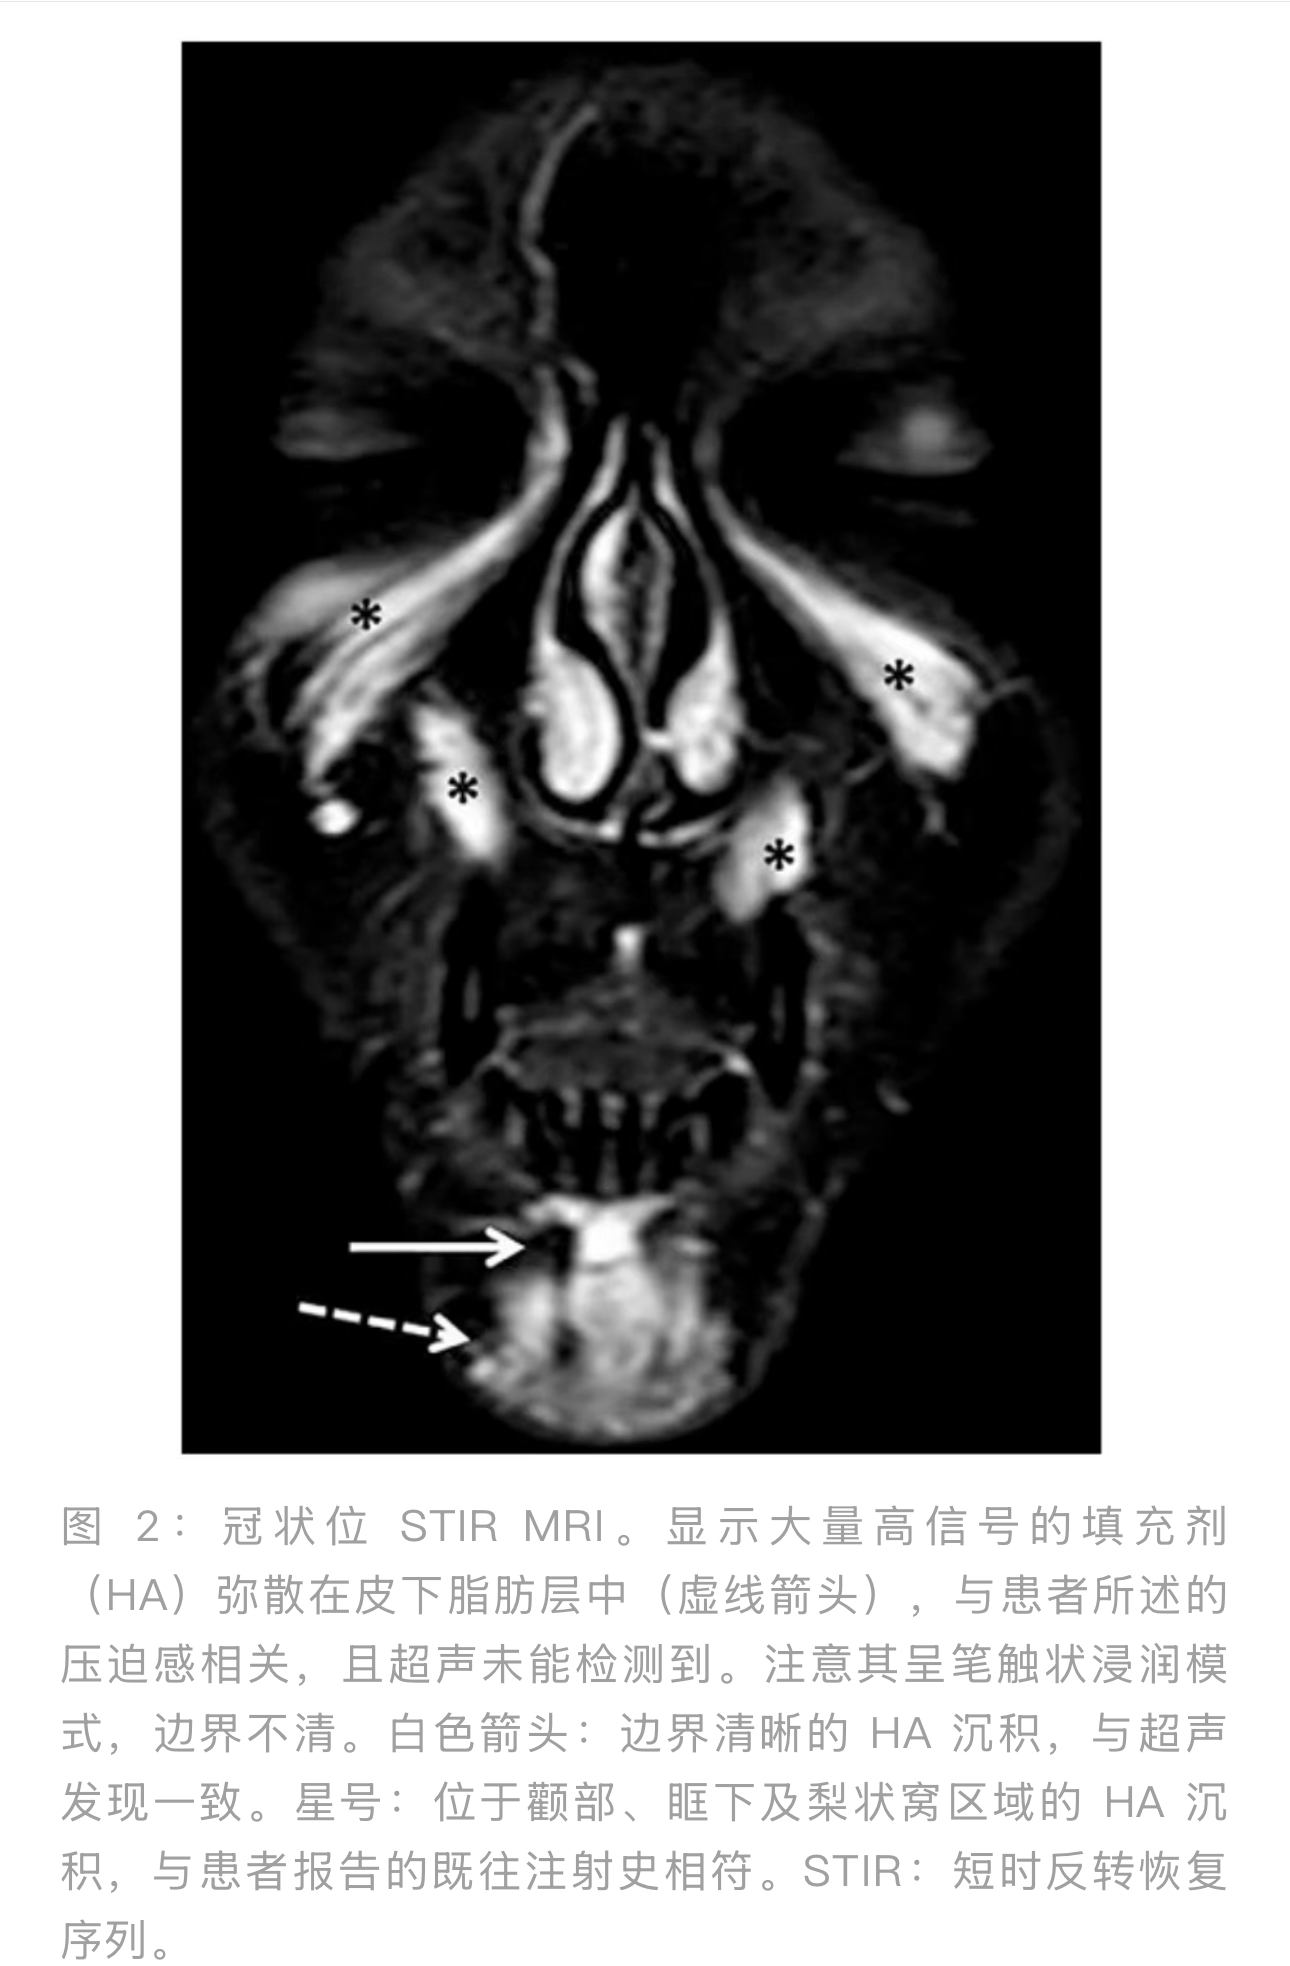

由于临床症状与超声发现不符,患者接受了高分辨率面部MRI检查。检查使用了比色映射和特定的面部序列(40分钟协议),未使用造影剂。除了确认骨膜上的HA沉积物外,MRI意外地显示,大量产品广泛弥散地分布在下巴的皮下组织中——包括浅层和深层——呈现"笔触状"模式,边界不清,缺乏结节形态(图2、图3)。

Hey guys,诊断透明质酸(HA)填充剂注射后的迟发性并发症可能具有挑战性,尤其是在临床症状轻微时。尽管超声(US)被广泛认为是评估面部填充剂的金标准,但在某些情况下有其局限性。我们报告一例30岁女性病例,她在使用高G'值HA填充剂(品牌未知)进行下巴填充两年后,持续感到下巴区域有压迫感。由经验丰富的放射科医生进行两次高频超声检查仅发现一个小的骨膜上团块,没有发现能解释症状的显著沉积物。而高分辨率面部磁共振成像

(MRI)却意外地揭示了大量HA广泛弥散在下巴的皮下脂肪中,这是超声未能检测到的。通过靶向注射透明质酸酶

(150 IU),症状得到完全缓解。随访MRI证实了HA沉积物的消退。本病例凸显了当填充材料广泛浸润脂肪组织且缺乏结节形态时,超声检查存在的诊断盲区。MRI虽然因成本和可用性问题未被常规使用,但在临床与影像学结果不符的情况下,可能提供关键的补充信息。本病例提示,在特定的临床-影像学不符的情况下,MRI可能提供有价值的补充信息。